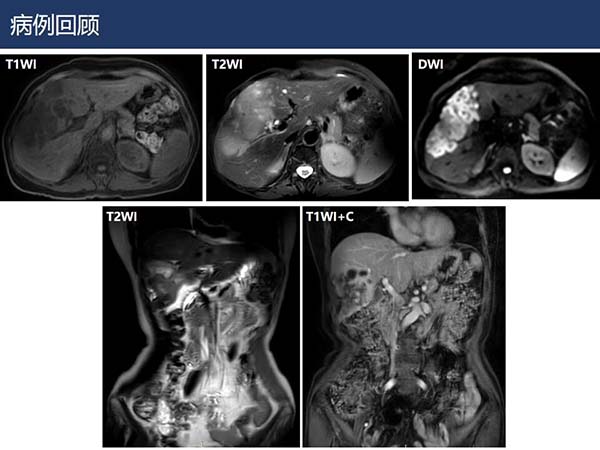

【杨柳病例】肝内胆管细胞癌的影像表现